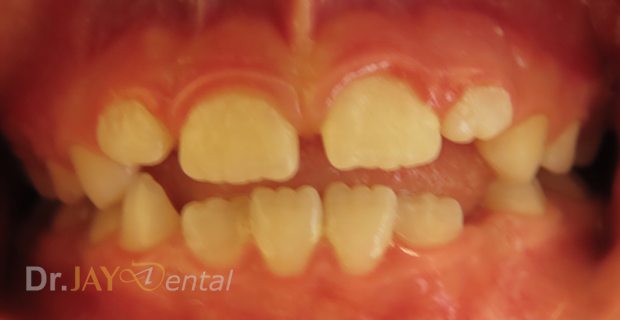

CASE 15

Patient had issue with spacing needed for erupting teeth , patient still going through treatment. After picture : in 6 months with Myofunctional therapy and tongue tie revision , jaws are widening and teeth are having space to erupt

Before

After